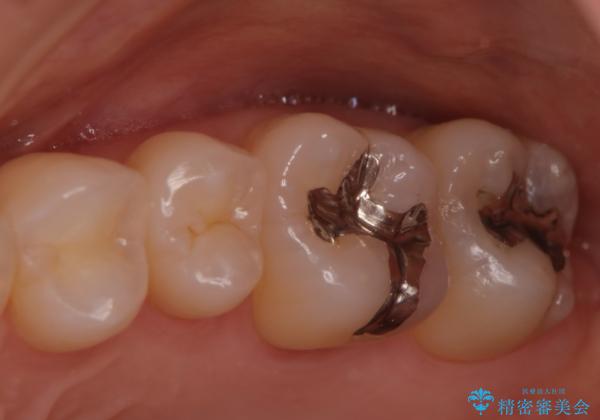

- 奥歯の銀歯が目立つということで来院されました。もともと入っていた銀歯を取り、虫歯の治療を行い、型取りを行ないます。

よく銀歯の下が虫歯になっていることがあります。

今回の患者様も銀歯を取ってみたら大きな虫歯になっていました。

虫歯をとり、銀歯から白いセラミックになったためかなり喜んでいただきました。